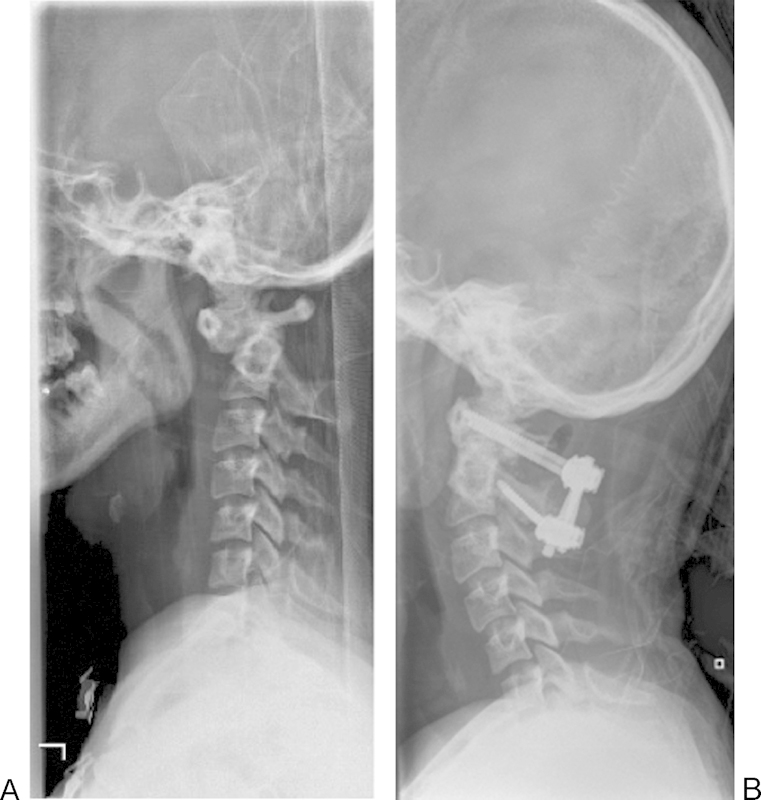

Study Design Retrospective case review. Objective Atlantoaxial instability with and without basilar invagination poses a considerable challenge in management regarding reduction, surgical approach, decompression, instrumentation choice, and extent of fusion. A variety of strategies have been described to reduce and stabilize cranial settling with basilar invagination. Modern instrumentation options included extension to the occiput, C1-C2 transarticular fixation, and C1 lateral mass-C2 pars among others. Since not all cases of cranial settling are the same, their treatment strategies also differ. Factors such as local vascular anatomy, amount of subluxation, need for distraction, and shape of occipital condyles will dictate level and type of instrumentation. The objective of this study was to outline treatment options and provide a rationale for the surgical plan. Methods Two cases of C1-C2 instability in patients with Down syndrome are described. Case 2 underwent C1-C2 instrumented fusion, whereas case 1 involved posterior instrumented fusion to the occiput. Results Both patients tolerated the procedures well. There were no complications. Minimum follow-up was 1 year. There was no loss of reduction. Solid arthrodesis was achieved in both cases. Conclusion Successful reduction can be achieved with both C1-C2 instrumented fusion as well as O-C instrument fusion. Factors such as local vascular anatomy, amount of subluxation, need for distraction, and shape of occipital condyles will dictate level and type of instrumentation.